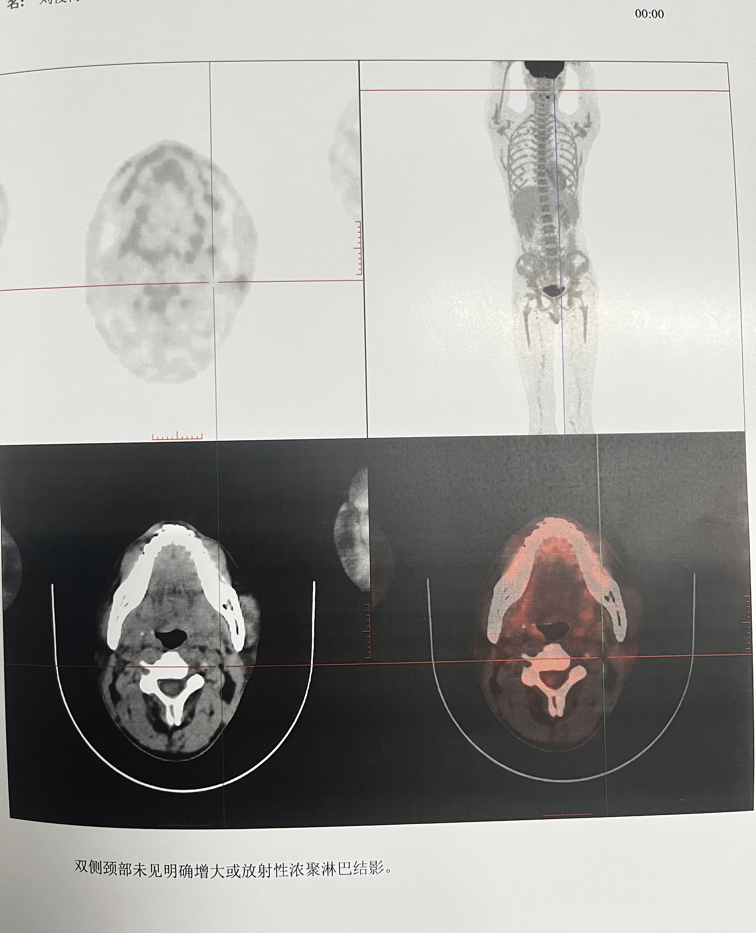

四疗后的中期评估

中期评估报告出来了不懂怎么看,

1分,CR,完全缓解了